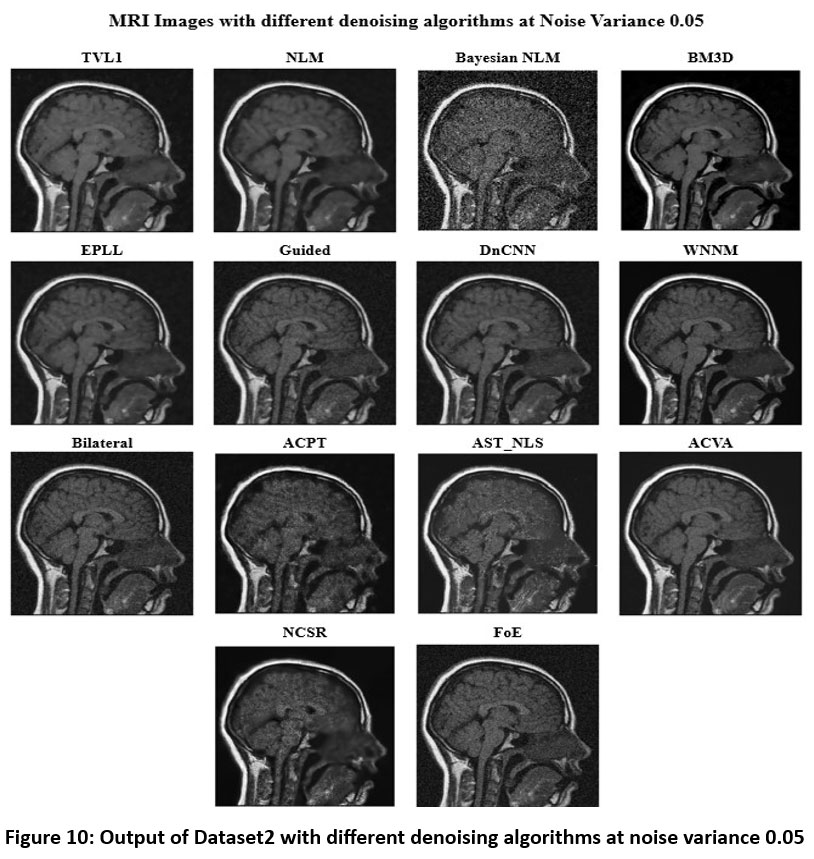

Figure 10 shows the denoised images using several methods at a noise of 0.05. BM3D is still among the topmost-ranking denoising techniques; the methods reduce the noise effectively while preserving the fine features of anatomy with high-quality texture and contrast. DnCNN is also a reliable choice for MRI image denoising since it also achieves a good trade-off between noise removal and feature preservation. Both WNNM and NLM perform well, but NLM leaves a bit more residual noise than WNNM. On the other hand, Bayesian NLM suffers from higher noise variance and results in a very grainy image with significant residual noise distortions. The performance of guided filtering, EPLL, and bilateral filtering is mediocre; they successfully reduce noise but also acquire a little smoothing effect that may cause fine details to be lost. Although ACPT may reduce the image quality because of the loss of structures, ACVA and AST_NLS are robust in producing visually clear images and keeping the details of the original structure. On the other hand, TVL1 is efficient in denoising images, but with an over-smoothing effect such that the remaining important contrast and texture are vanished. This makes FoE and NCSR be the weakest among the list of algorithms here. NCSR results in extreme blurring, which compromises the structural integrity of the image and reduces its diagnostic value. Guided filtering, EPLL, and bilateral filtering perform poorly; they can remove noise but have a small amount of smoothing effect that may lead to loss of fine details.

![]() |

Figure 10: Output of Dataset2 with different denoising algorithms at noise variance 0.05 |